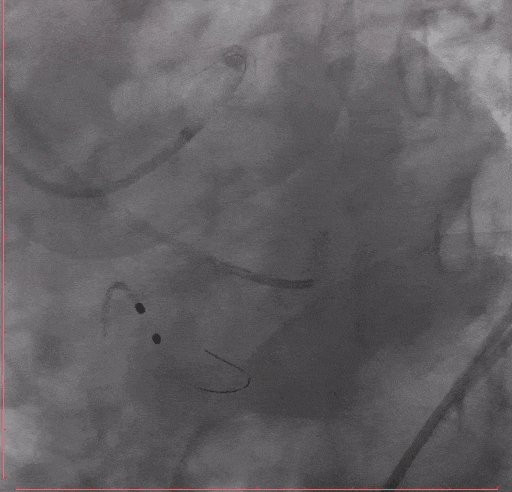

Step 5 左主干植入支架 回旋支开口予以切割+药物球囊

Step 6.主动脉瓣球囊预扩张

Step 7. Taurus 26 瓣膜释放至工作位造影确认位置